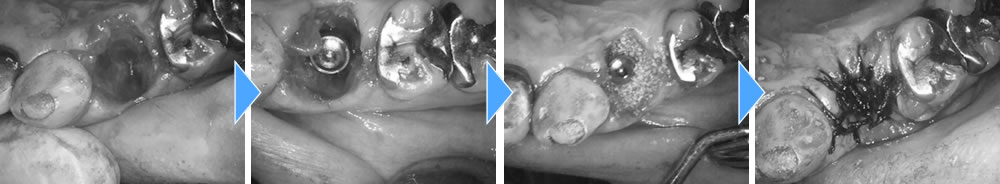

Before

After